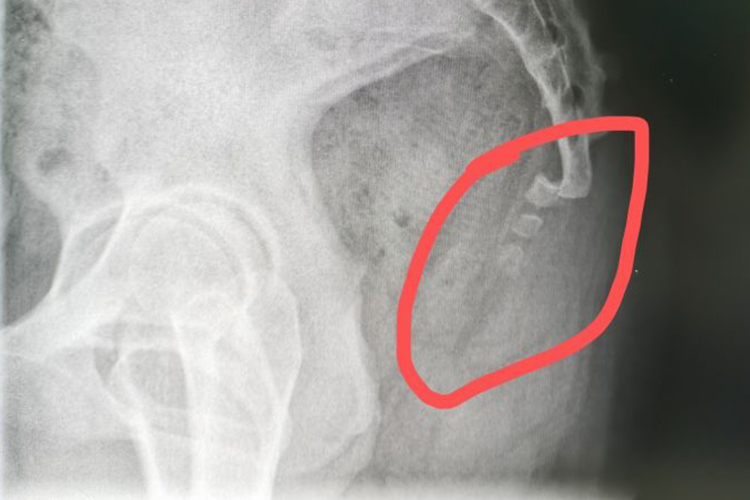

骶尾发育异常综合征:骶尾发育异常综合征主要表现为椎体不发育,从部分尾骨至腰椎以下全部不发育,且有不同类型、不同程度的短肢畸形、髋关节脱位、臀部扁平等。此外,严重者有髓骨融合,胃肠道功能素乱及神经性膀胱,X光下可以看到尾骨的突出。

尾骨骨折:尾骨骨折后局部疼痛剧烈,尤其坐位时疼痛加重。检查时局部有明显的压痛,但是肿胀不明显,肛诊时可以触及尾骨的前后错动。尾骨骨折脱位后,由于附着于其上的肛提肌、尾骨肌和肛门外括约肌以及韧带的张力发生变化,患者可出现肛门坠胀感。X线片可以确诊,侧位片可以看到尾骨向前移,正位片上可以见到尾骨的远端向侧方移位。